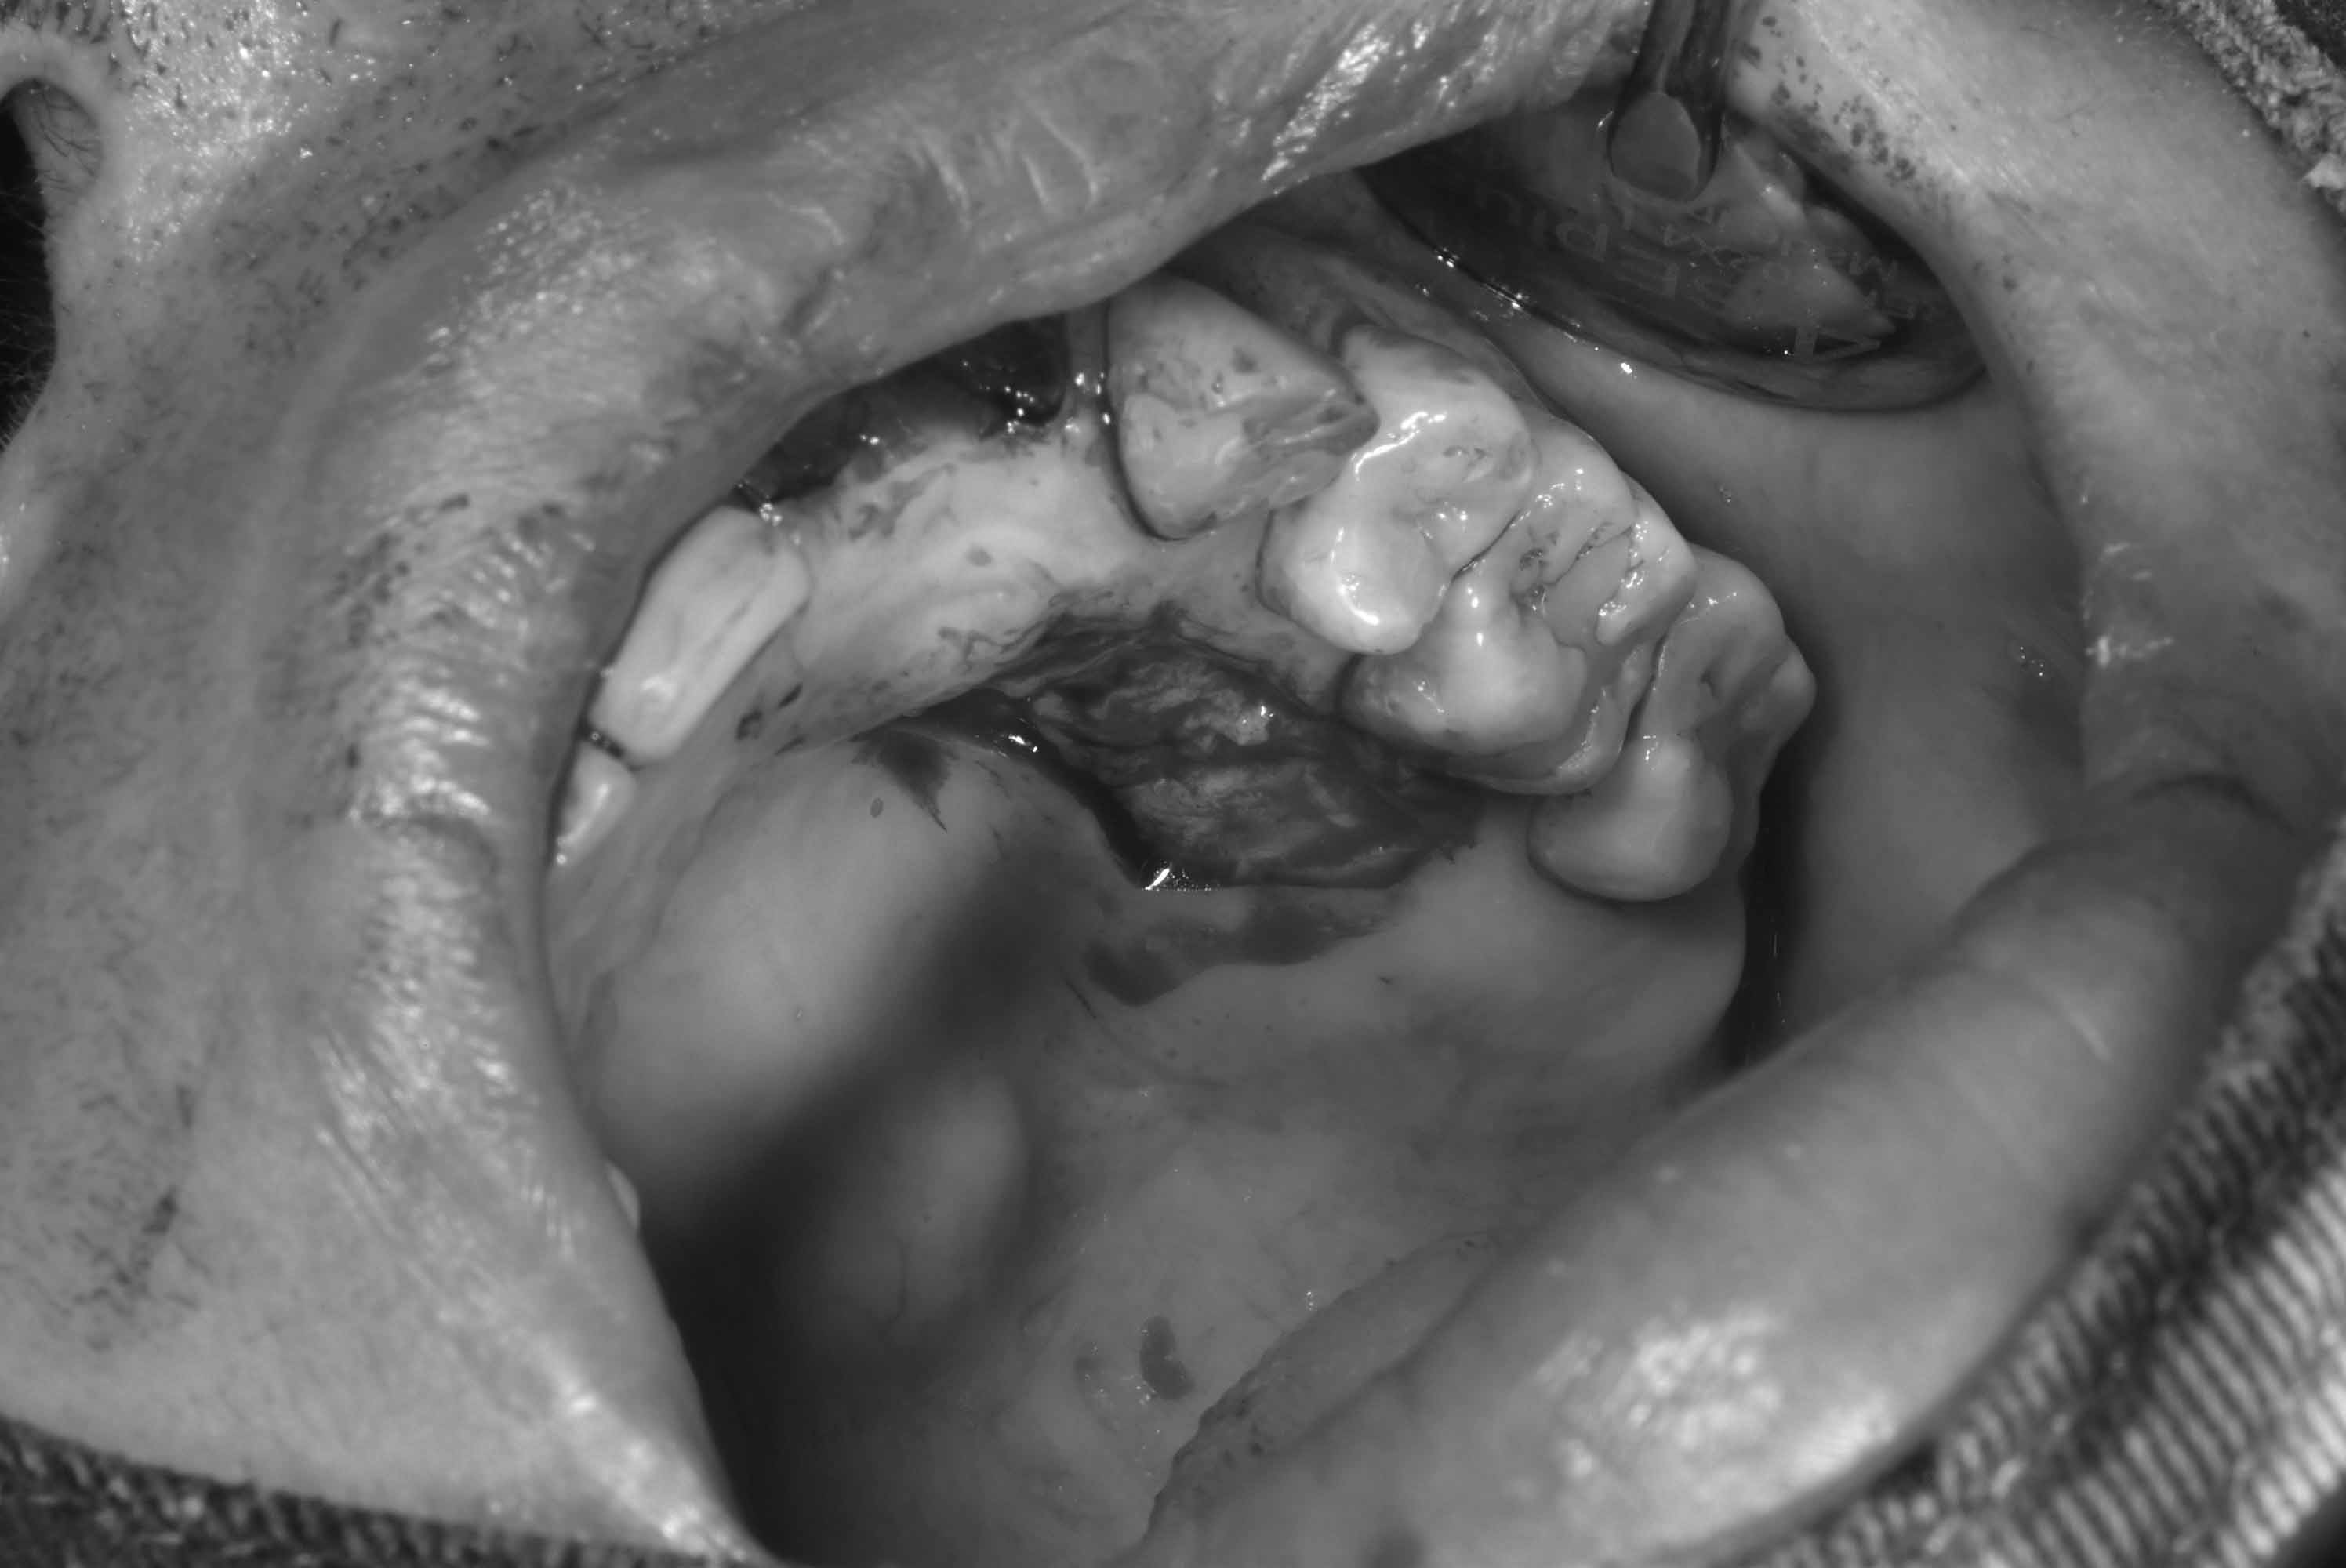

牙齦移植術(補肉)

手術案例

術前加術後案例

案例三